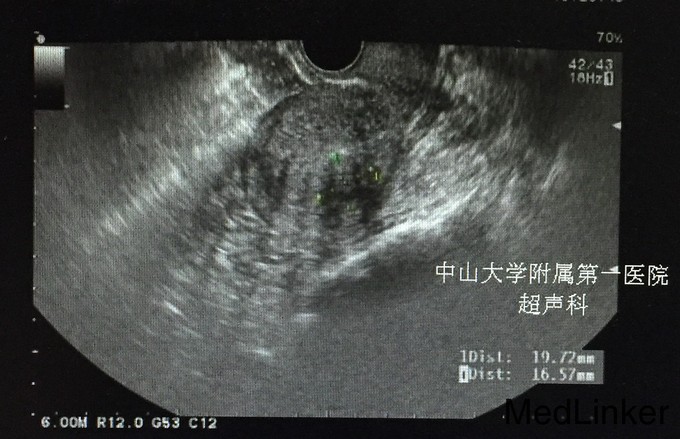

查体:;宫颈轻度糜烂,余未见异常。 辅查:.2015-10-04妇科B超:子宫增大,子宫肌瘤(后壁2.2cm*2.1cm),子宫内膜增厚,约1.8cm。 2015-10-10诊刮病理示:慢性子宫内膜炎,局部符合子宫内膜息肉,分泌期子宫内膜。 2015-10-25我院妇科B超:小型子宫肌瘤。(见图)

诊断:1.异常子宫出血:子宫内膜息肉(多发性)?2.月经过多 治疗:宫腔镜检查+子宫内膜射频消融术, 宫腔镜下见:宫颈管通畅,宫腔形态正常,双侧输卵管开口清晰,子宫内膜不厚,未见明显赘生物和突起,刮出内膜送病理。探子宫腔深9.0厘米,宫颈深度4.0cm。设置宫腔深5.0cm,宽4.6cm,功率121w,启动后射频工作时间69s。 再次宫腔镜下检查,见宫腔包括两侧宫角基本消融,呈焦黄色。宫颈管内膜未破坏。术毕。